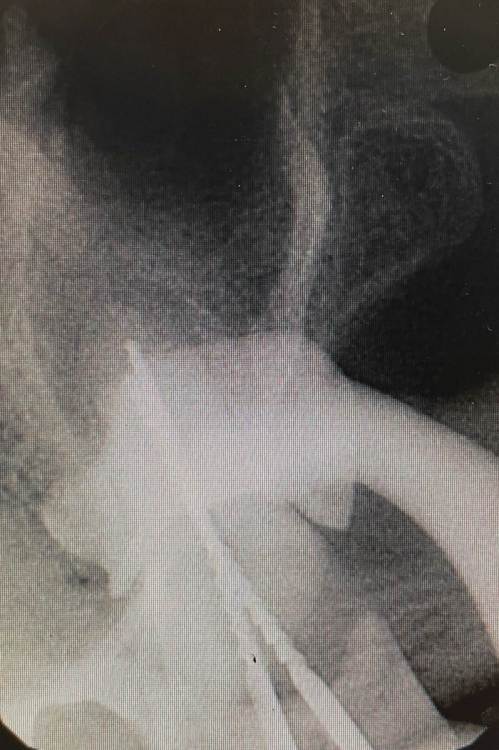

Кирилл Якимов Опубликовано 5 мая, 2022 Поделиться Опубликовано 5 мая, 2022 Добрый день, дорогие коллеги! Я начинающий врач, очень нужна конструктивная критика) 2.7 зуб, каналы лечили несколько лет назад(пациентка точно не помнит). Зуб не беспокоит. Сделал прицельные снимки + КТ. Есть очаг перирадикулярной деструкции+гуттаперча за апексом+резорбция. Принял решение зуб перелечить. Убрал старую пломбу и кариес, гутта в каналах мягкая, распломбировал довольно быстро Profile 25.06 25.04 и желтый Mtwo со стеночек+активация гипохлорита 3% U-file 15 стальным. Из-за апекса гуттаперчу вытащил H-file. В первый визит расширил до 70 K-file. Длина обеих каналов 18мм. Оставил кальций на 2 недели. Коллега микроскопист говорит, что нужно делать пробку МТА, дальше обтурация гибридной методикой, затем коронка и контрольное КТ через 6 мес. Подскажите пожалуйста, как и чем все таки лучше пломбировать такой зуб и какой наиболее вероятный прогноз? Кто что думает, в чем может быть причина такой резорбции? Ссылка на комментарий

Кирилл Якимов Опубликовано 8 мая, 2022 Автор Поделиться Опубликовано 8 мая, 2022 Удалось, но апекс же широкий и резорбция. Такой апекс можно обтурировать гуттой? Ссылка на комментарий

Гарриевич Опубликовано 14 мая, 2022 Поделиться Опубликовано 14 мая, 2022 08.05.2022 в 20:54, Кирилл Якимов сказал: Удалось, но апекс же широкий и резорбция. Такой апекс можно обтурировать гуттой? Если есть упор, то не имеет значения какого он диаметра. Хоть 20, хоть 120. Модно закрывать гуттой. она сработает как пробка 1 1 Ссылка на комментарий